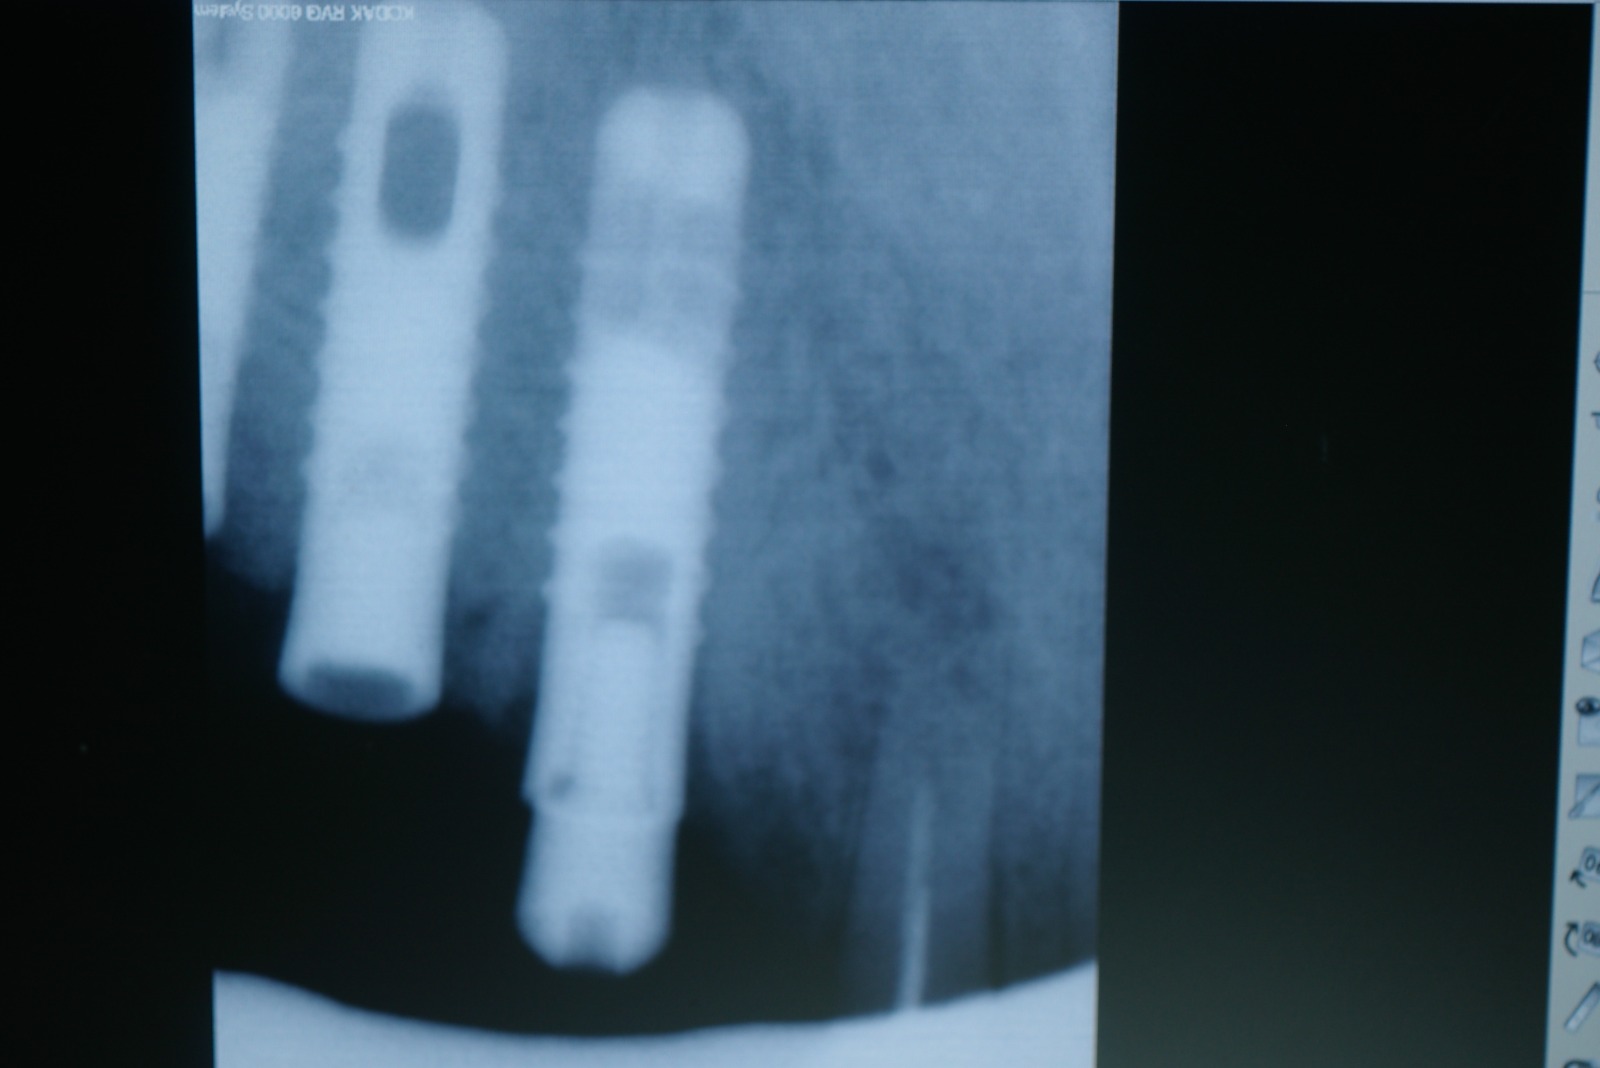

El paciente no presenta incidencias hasta el año 2005, cuando acude a consulta con el segmento distal derecho desprendido y en el que se había producido una fractura de los aditamentos macizos a nivel de la unión del aditamento con implante, de forma que la rosca fracturada del aditamento está encajada dentro de los implantes.

El tratamiento que se intento fue extraer las roscas rotas con ultrasonidos, pero no se pudo, por lo que procedimos a realizar el vaciado de estas roscas rotas y a realizar unas espiras nuevas en estos vaciados con un set de machos roscantes, para después roscar nuevos aditamentos originales de la casa ya fabricados en aleación de titanio (grado V) . Una vez instalados los aditamentos procedimos a su tallado y a realizar la prótesis ceramo–metálica como tenía antiguamente.

Actualmente vuelve el paciente de nuevo con la misma prótesis. Había roto dos de los tres pilares en concreto los más distales. El primero de los dos había roto la rosca del aditamento dentro del implante como ocurre habitualmente. Pero el ultimo pilar había roto directamente la cabeza del implante tal como se ve en la radiografía y lo que quedaba era un cilindro de titanio macizo perfectamente integrado en el maxilar, sin posibilidad de enroscar nada. Le explicamos al paciente que habría que quitar y poner un implante en el mismo acto. El paciente dijo que no, así que decimos que no se haría cirugía. Buscamos solución alternativa: hacemos un un agujero en el centro del macizo cilíndrico del implante roto y pasamos sucesivamente el set de machos roscantes. Utilizamos una fresa cañón de 1 mm que poco a poco se va introduciendo hasta 8mm con un poco de vagación, que hace que sea un poco mas de 1mm de diámetro. Posteriormente pasamos el conjunto de machos roscantes de métrica 2mm para poder usar un aditamento experimental, que era un palo de rosca de diámetro 2 mm unido a un cuerpo metálico en forma de sombrero napoleónico fabricado en cromo/cobalto, prototipos primitivos de la sistemática ASATIM y que tienen la característica de tener gran resistencia a la fractura. Nos llevó un tiempo largo el tallado de dichos aditamentos, tal como se puede observar en las imágenes, y tras cicatrizar la encía se le hizo una prótesis estándar. Esperemos que no lo rompa más veces.